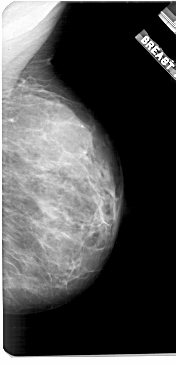

A_1921_1.RIGHT_MLO

RIGHT_MLO LINES 5461 PIXELS_PER_LINE 2626 BITS_PER_PIXEL 12 RESOLUTION 43.5 NON_OVERLAY